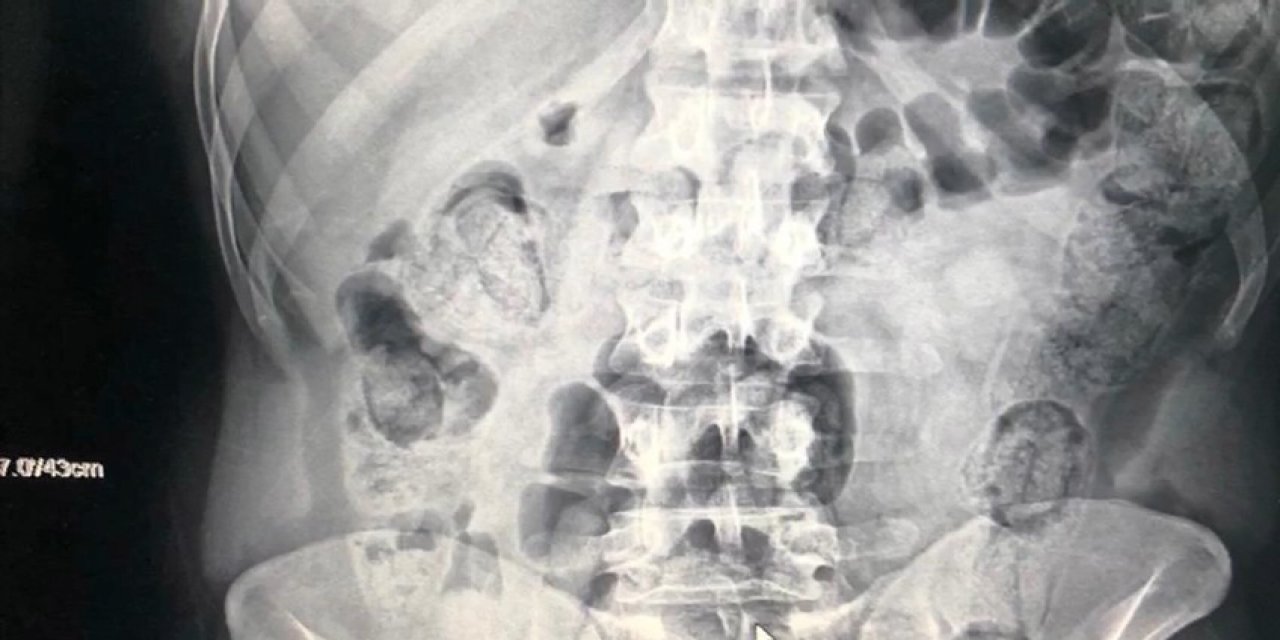

Edinilen bilgiye göre, Kocaeli TEM Otoyolu'nda bir yolcu otobüsünü durdurarak arama yapan Narkotik polisleri, hareketlerinden şüphelendikleri İran uyruklu şahsın bagajlarında yaptıkları aramalarda üzerinde dışkı kalıntısı olan prezervatiflere sarılı 25 paket metamfetamin adlı uyuşturucu maddesi ele geçirdi. Uyuşturucuları yuttukları şüphesiyle hastaneye götürülen şahısların çekilen röntgenlerinde, midelerinde kapsüller halinde uyuşturucu olduğu belirlendi.

Tespit sonrasında şahısların midelerinden hekim kontrolünde 103 paket halinde 871 gram metamfetamin maddesi çıkartıldı. Emniyet Müdürlüğüne götürülen 3 şahsın, tamamlanan işlemleri sonrasında adliyeye sevk edilmesi bekleniyor.